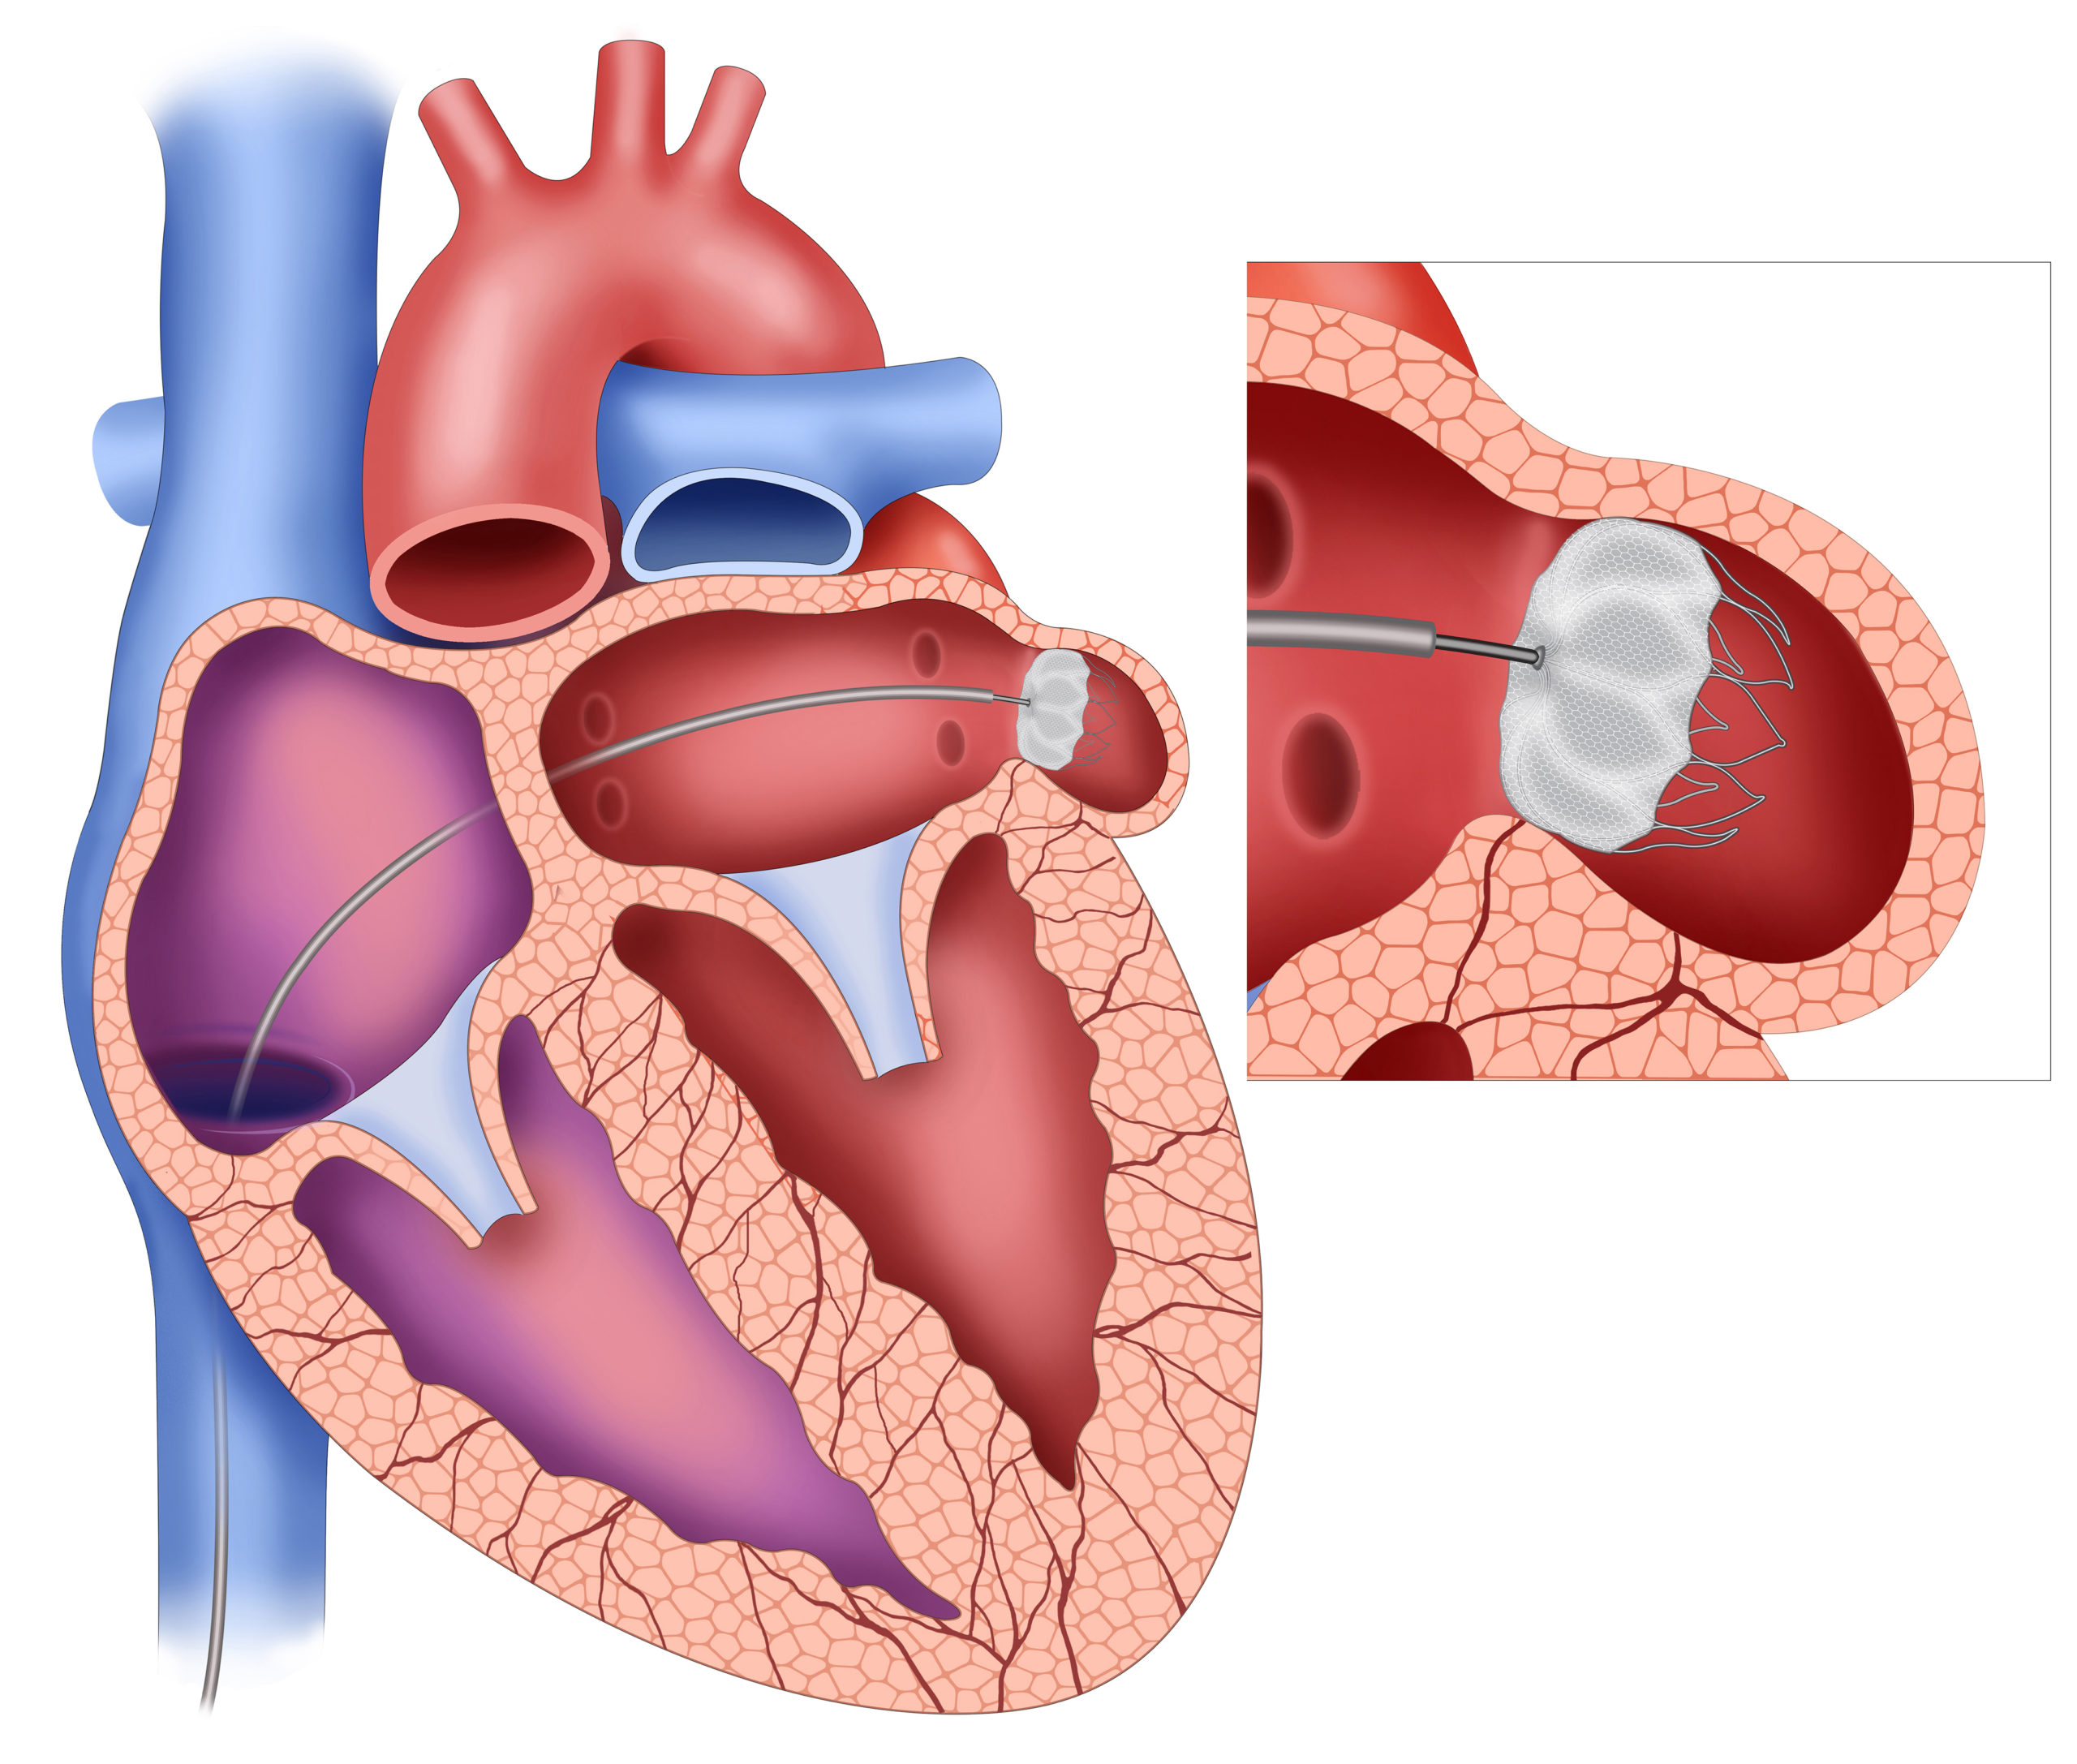

left atrial appendage closure

According to Mostafa Reda Mostafa and collaborating researchers, left atrial (LA) appendage closure (AC) showed an ...

In a meta-analysis published in the Anatolian Journal of Cardiology, researchers assessed the effectiveness of catheter ...

According to a study published in Cardiovascular Intervention and Therapeutics, the safety and efficacy profiles of left ...